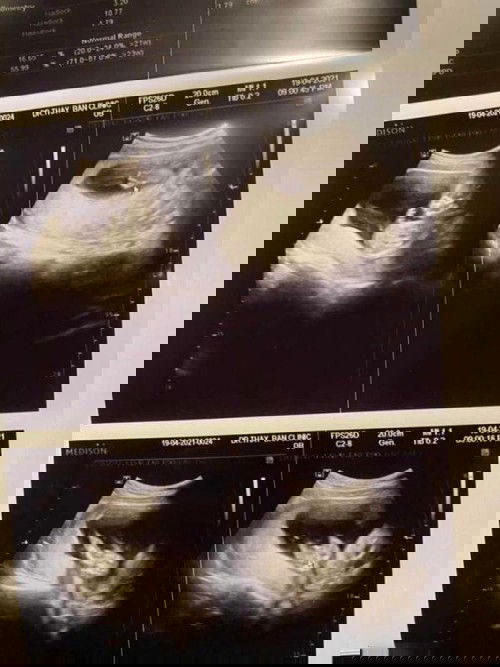

ซาวน์ครั้งแรก จู๋ก็โผล่เลยจ้า ในรูปไม่ค่อยชัด แต่ตอนซาวน์ชัดเจนมากค่าา หมอว่าหนูตัวใหญ่เกินเกณฑ์ คุณแม่ต้องกินน้อยลงหน่อย 🤣🤣 เราเป็นคนตัวเล็ก แต่ไม่เล็กมาก คุณหมอบอกว่า ถ้ายังคงทานเยอะละลูกตัวใหญ่ อาจจะต้องผ่าคลอด แต่เราอยากคลอดเองง คุณแม่มีคำแนะนำอะไรบ้างไหมคะ ถ้าอยากคลอดเอง #ขอบคุณล่วงหน้านะคะ